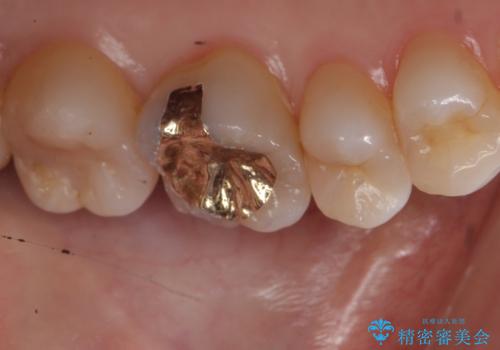

ゴールドインレーにて治療しました。

最小限で詰め物の治療をしました。

- ゴールドインレー 7.7万円費用は治療当時の料金となります

ゴールドの詰め物は歯質との隙間ができにくく

虫歯の再発リスクが少なくなります。